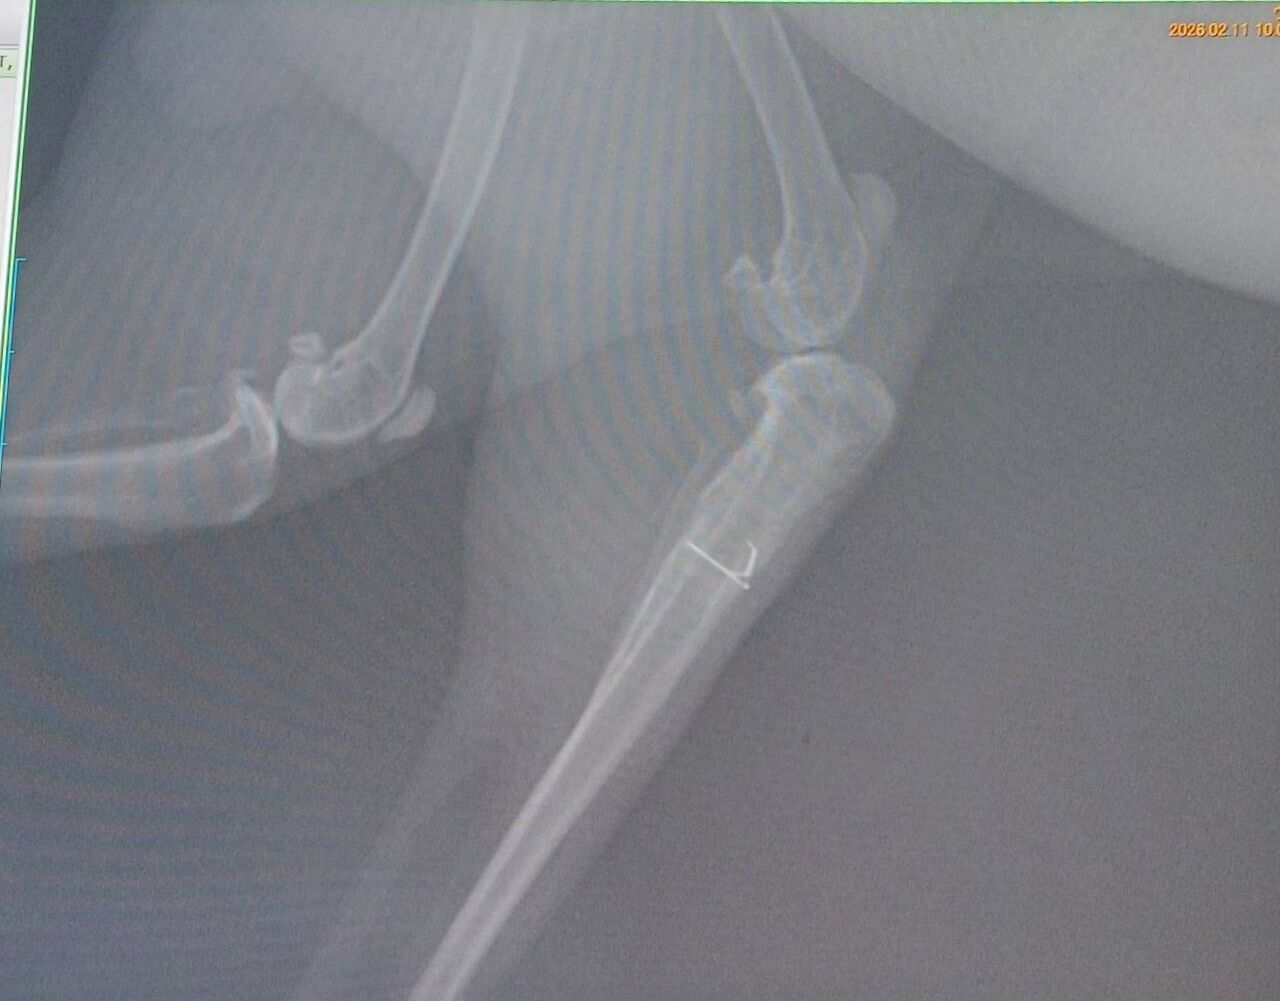

2025年11月に右後ろ脚を骨折し、11/14にピンニング手術を受け、現在も経過観察中です。

2/11 1800g 経過確認のため受診しました。

足裏の汚れは左右差はなく、足はよく使えており、ソアホックもありませんでした。

レントゲンでは骨の状態も良好で、筋肉もついてきており順調とのこと。

ここまで回復してくれたことに安堵しています。

ワイヤーが残ってるため、今後は先端が刺激になって炎症起こす可能性があり、

様子に変化があれば受診し、ワイヤー除去または先端を切る処置が必要になる可能性があると説明を受けました。

日常生活は通常通り可能とのことですが、様子を見ながら慎重に過ごしています。

次回再診は6月予定です。